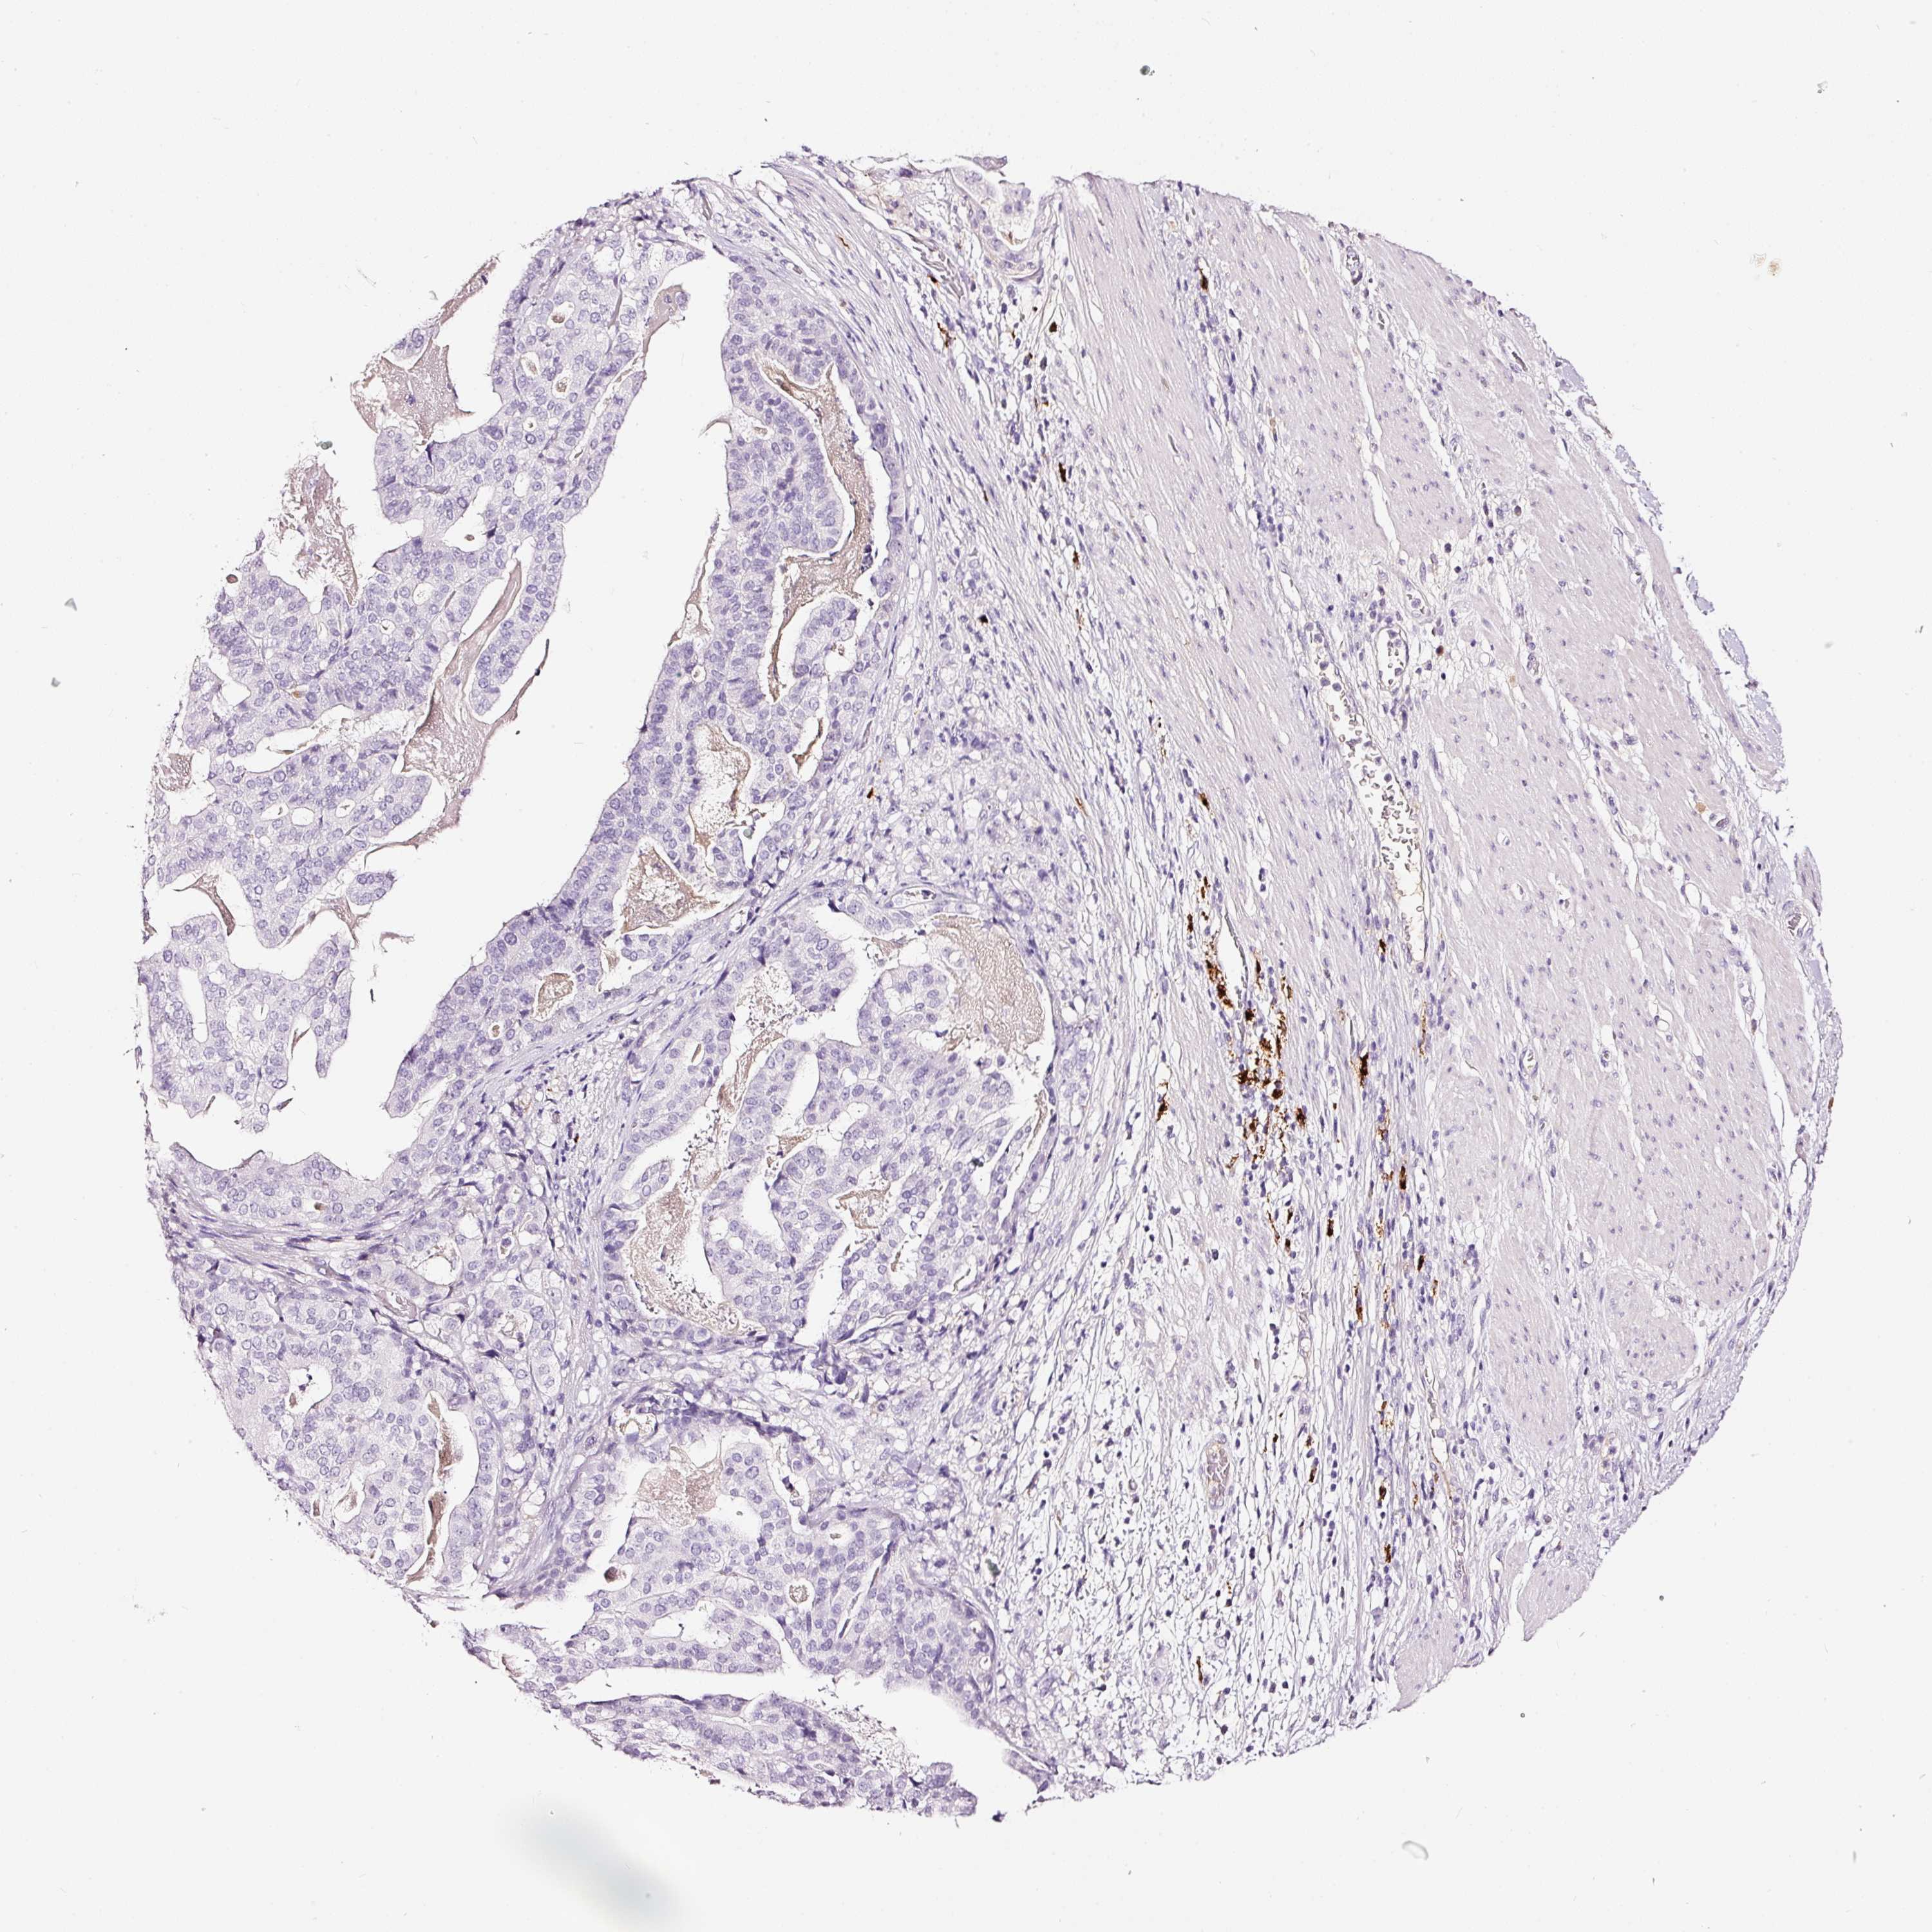

STOMACH CANCER - Protein expressioni

A mouse-over function shows sample information and annotation data. Click on an image to view it in a full screen mode. Samples can be filtered based on level of antibody staining by selecting one or several of the following categories: high, medium, low and not detected. The assay and annotation is described here.

Note that samples used for immunohistochemistry by the Human Protein Atlas do not correspond to samples in the TCGA dataset.

Antibody stainingi

Antibody staining in the annotated cell types in the current human tissue is reported as not detected, low, medium, or high, based on conventional immunohistochemistry profiling in selected tissues. This score is based on the combination of the staining intensity and fraction of stained cells.

Each image is clickable and will lead to virtual microscopy that enables deeper exploration of all samples and also displays staining intensity scores, fraction scores and subcellular localization as well as patient and tissue information for each sample.

Antibody HPA051467

Antibody CAB025133

Staining

High

Medium

Low

Not detected

Intensity

Strong

Moderate

Weak

Negative

Quantity

>75%

75%-25%

<25%

None

Location

Nuclear

Cytoplasmic/membranous

Cytoplasmic/membranous,nuclear

Adenocarcinoma, NOS